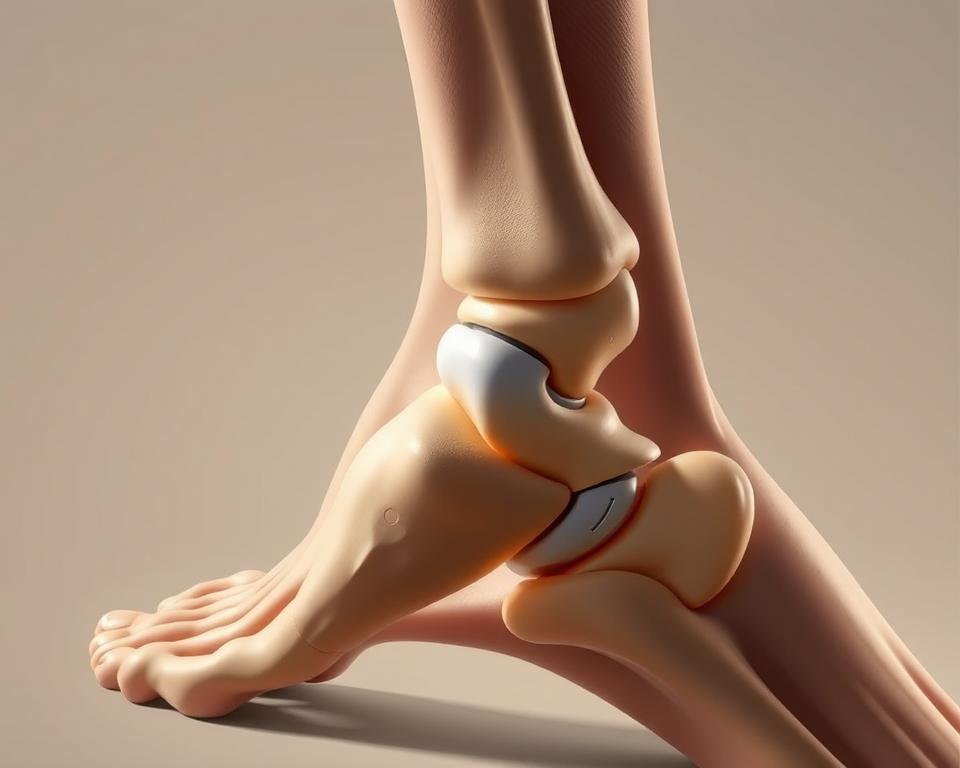

Anatomia torebki stawowej

Zrozumienie budowy tej struktury pomaga lepiej zorientować się w mechanizmach urazów. Torebka stawowa przypomina inteligentnie zaprojektowaną osłonę – łączy elastyczność z wytrzymałością, by sprostać codziennym wyzwaniom.

Budowa: błona maziowa i warstwa włóknista

Wewnętrzna część składa się z delikatnej błony maziowej. Ta żywa fabryka produkuje lepką maź, która działa jak naturalny smar – zmniejsza tarcie podczas ruchu i dostarcza składniki odżywcze do chrząstki.

Zewnętrzna warstwa to gęsta sieć włókien kolagenowych. Układają się one w specyficzne wzory, które decydują o stabilności stawu. W kolanie tworzą mocne pasma, w palcach – bardziej elastyczną siatkę.

Funkcje ochronne i stabilizujące w stawie

Błona maziowa pełni podwójną rolę. Jej gęsta sieć naczyń krwionośnych działa jak filtr – kontroluje przepływ substancji między krwią a płynem stawowym. Jednocześnie produkuje białka chroniące przed infekcjami.

Warstwa włóknista przypomina inteligentny gorset. W spoczynku utrzymuje luźną strukturę, pozwalając na swobodny ruch. Przy nagłym skręceniu natychmiast napina się, blokując niebezpieczne przemieszczenia kości.

Różnice w grubości poszczególnych części tłumaczą, dlaczego kostka goi się inaczej niż nadgarstek. Im większe obciążenia musi znosić staw, tym gęstsze i mniej rozciągliwe są jego warstwy ochronne.